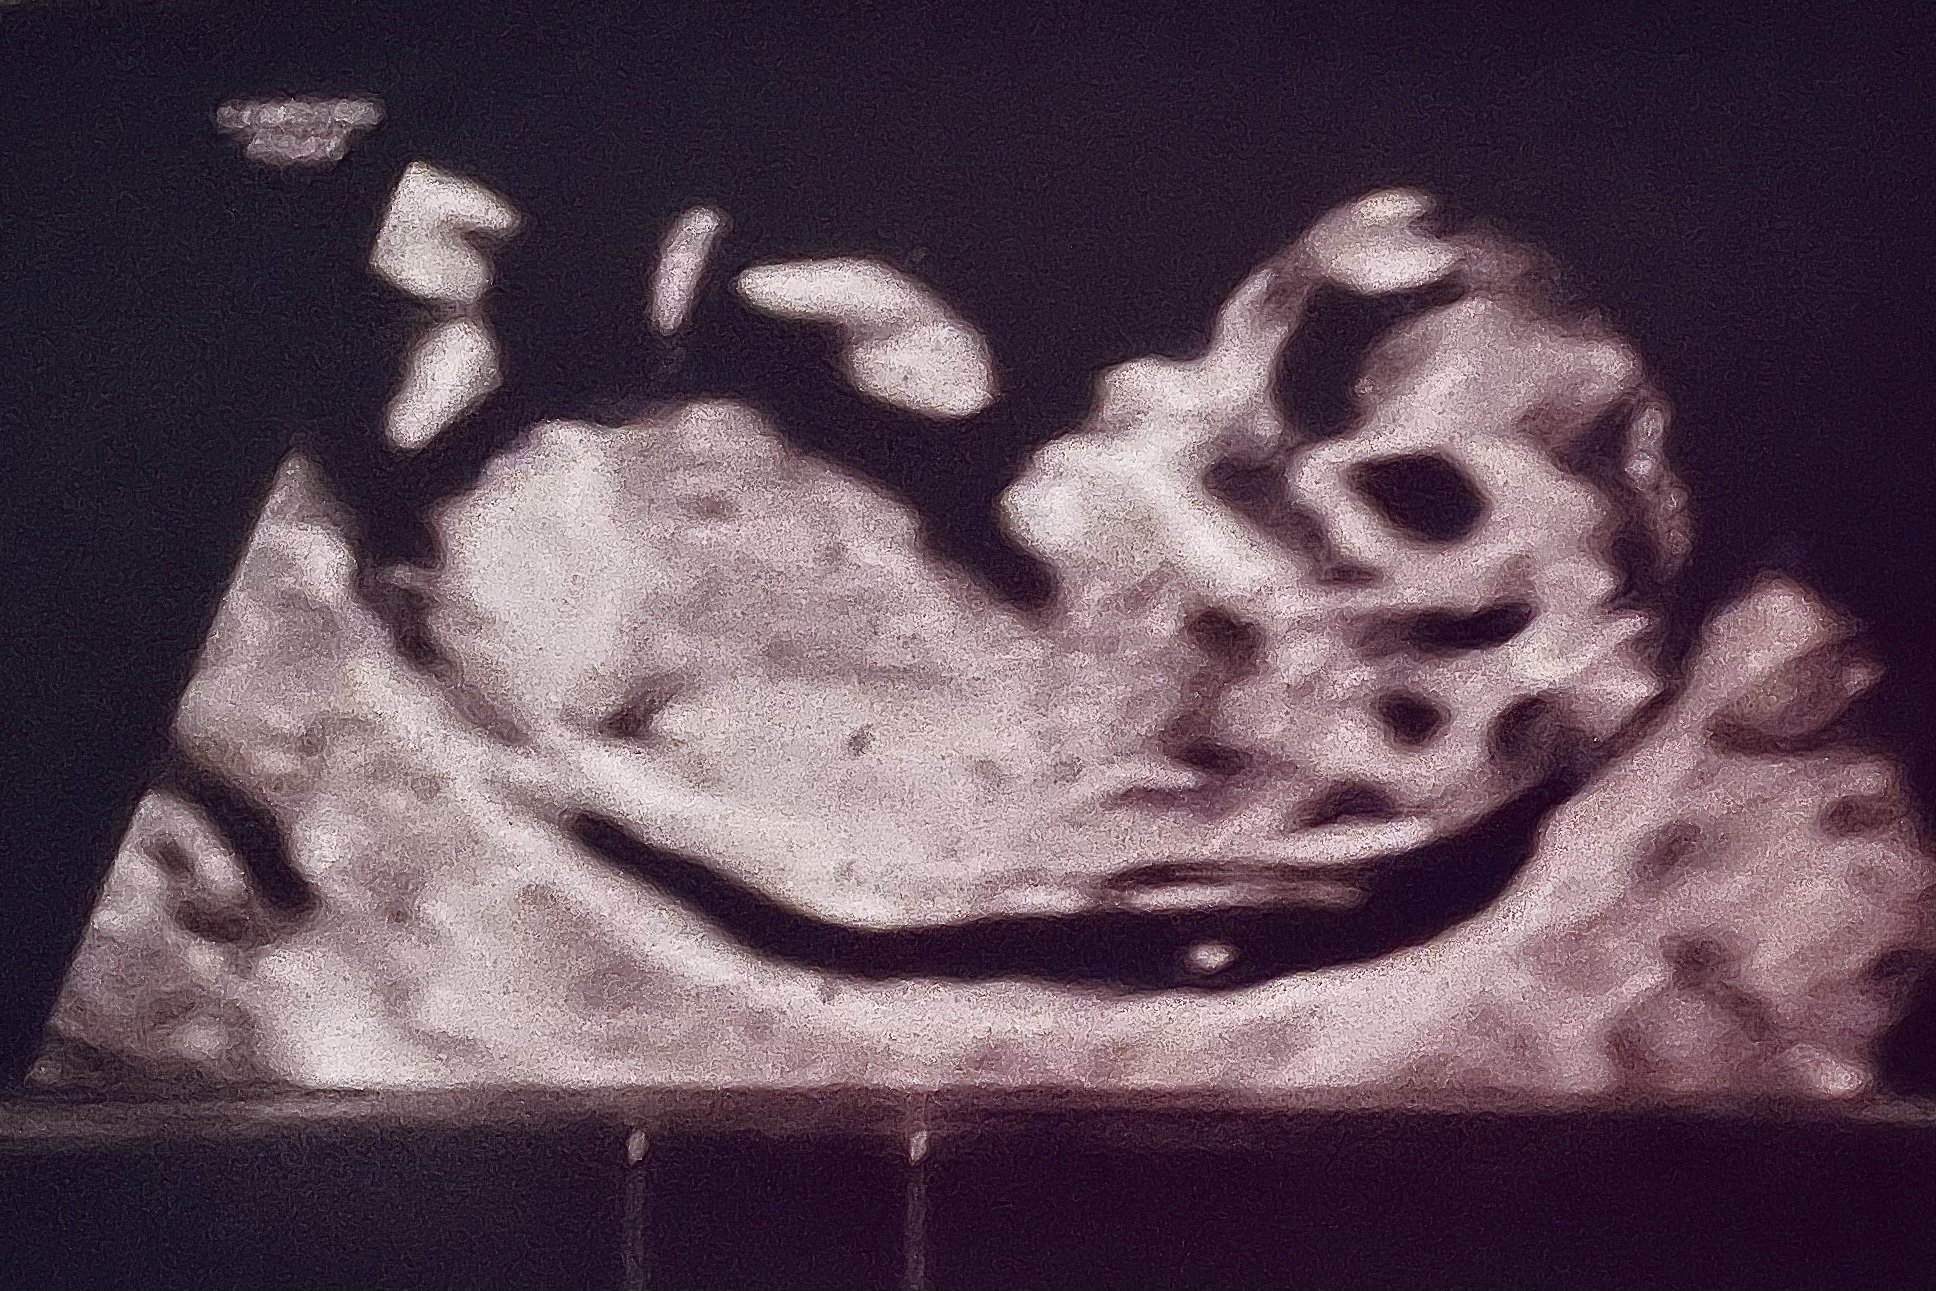

I am new TB! We are 15 weeks today! This US was taken on the 16th & the GA is incorrect on the US, the paper work i got after the doctor saw it, shows that i was further along then i thought! We have a due date of Jan 14th! We announced last week on facebook, I wanted to wait till we were clear out of the first trimester. I did the blood work, still waiting on the gender!

(ps. this is not the username I chose and the one I changed It too still isn’t showing up so excuse the ridiculous username)